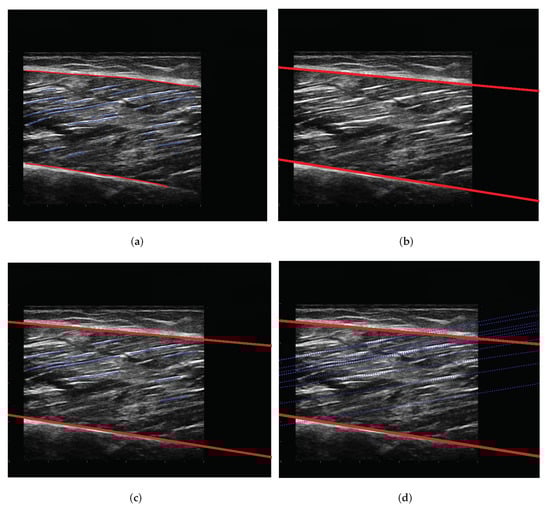

3.4. Post-Processing